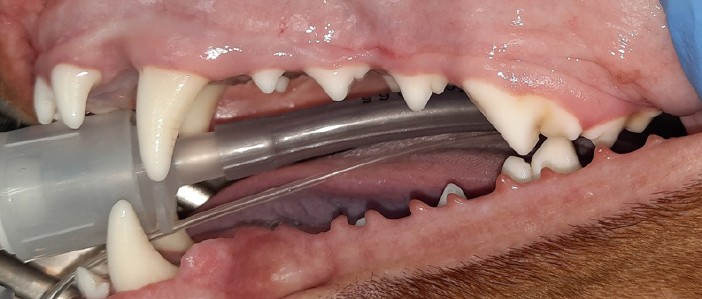

Fig. 4. Dental calculus stage 1 (109, 108, 104)

Source: VTC "Dentalvet".

Fig. 5. Intraoral radiograph for stage 1 dental calculus